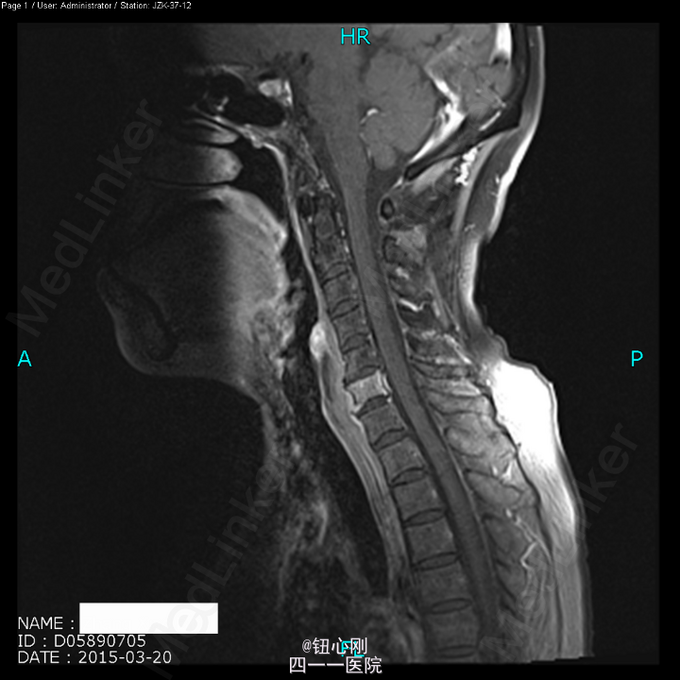

术前诊断:多椎体病变待查(转移瘤?) 诊断依据:老年女性,出现颈腰部疼痛,MRI及PET-CT扫描提示椎体多节段病变,以转移瘤可能性为大,同时血沉升高。 处理:2015-03-31在全麻下行颈6椎体病变前路次全切+钢板钛网植骨融合内固定术。术中所见:颈6椎体骨质疏松,部分硬化,未见鱼肉样组织。术后切除骨质送病理检查。 病理报告:骨小梁稀疏,其间有纤维组织,同时可见硬化死骨。 术后诊断:颈6椎体骨质疏松性骨坏死。

随着医学影像学及脊柱微创手术的发展,骨质疏松性椎体骨坏死逐渐被认识。该病临床上并非少见,骨坏死会导致椎体逐渐塌陷与进行性后凸畸形,引起患者长期腰背痛,甚至出现脊髓神经受压而瘫痪。患者为老年,主诉脊柱疼痛,MRI有椎体信号改变,因而易与脊柱转移性肿瘤混淆。骨坏死椎体在T1WI加权像上呈界限清楚的低信号区域,在T2WI加权像及脂肪抑制序列像上呈界限清晰高信号区域。这是与脊柱转移性肿瘤相鉴别的要点,对于累计整个椎体的骨坏死更需注意鉴别。 如疼痛不缓解或发生后凸畸形,可行椎体后凸成形术。